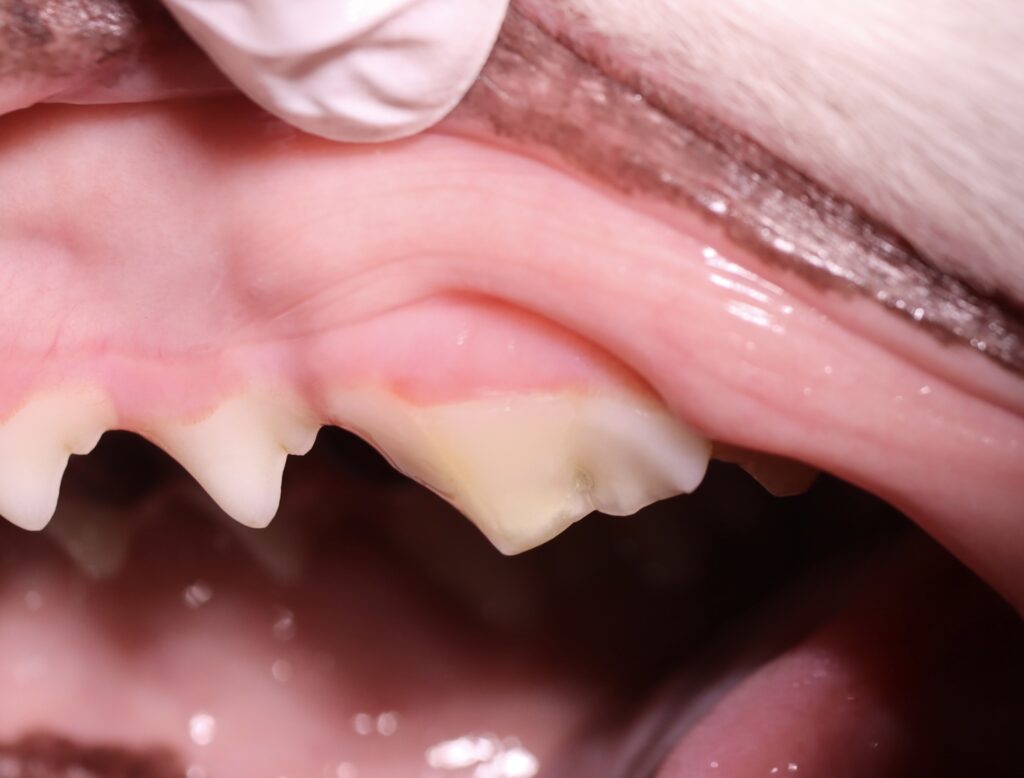

下の写真は第四前臼歯が折れてしまったわんちゃんです。

この症例は上記適応に全て当てはまり、神経を温存する生活歯髄切断治療を行いました。